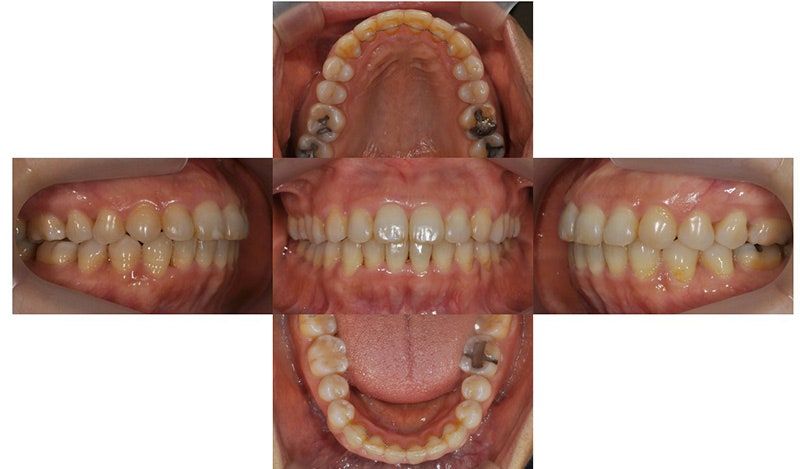

2020.3

위 환자는 만 48세 여자 환자로, 오른쪽(사진상 왼쪽) 두번째 앞니가 정상보다 작은 사이즈의 왜소치(peg lateralis)를 가지고 있었으며 이로 인해 치아의 중심선이 틀어져 있었고, 위아래 치아가 깊게 물리는 과개교합 양상을 보이고 있었습니다. 틀어진 치열로 인해 구강위생관리가 쉽지 않아 아래 앞니에는 치석도 많이 있는 상태였습니다. 틀어진 아래 앞니가 컴플렉스였기 때문에 아래만 부분 교정으로 먼저 시작하셨다가, 아래 부분 교정 마무리 후 위에도 개선하고 싶다고 하셔서 위 치아까지 전체교정으로 진행한 케이스입니다.

2021.8

오른쪽 왜소치 때문에 치아 중심선의 차이가 남은 상태로 마무리 되었으나, 환자분께서는 치료 결과에 만족하셨습니다.